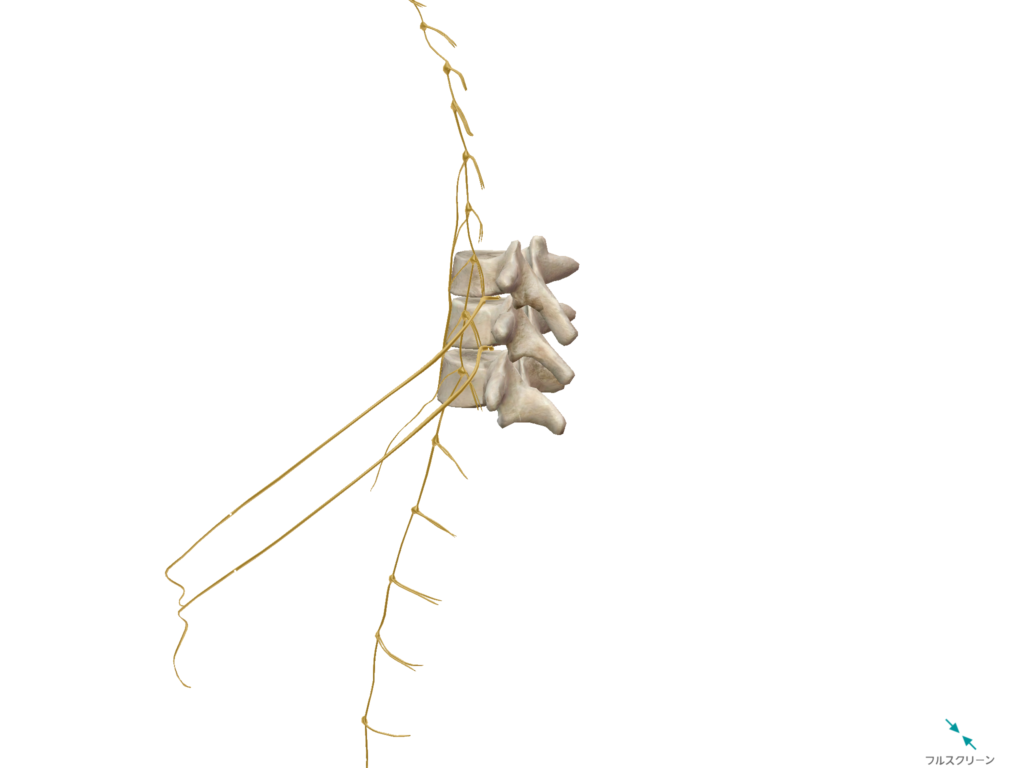

出展:VISIBLE BODY®

出展:VISIBLE BODY®

〇内臓との連絡通路である脊柱周辺を圧し

内臓と脳の神経の通りを良くしたり、